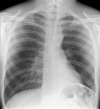

Normal CXR